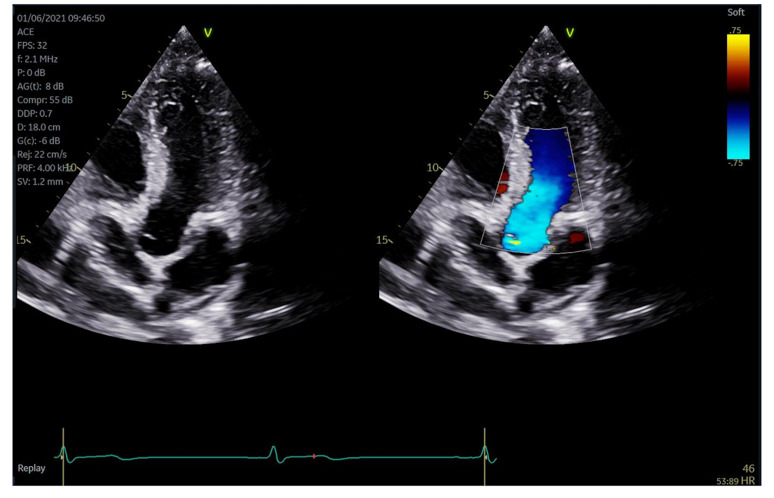

Background: The number of patients referred for and requiring a transthoracic echocardiogram (TTE) has increased over the years resulting in more cardiac sonographers reporting work related musculoskeletal pain. We sought to determine if a scanning protocol that replaced conventional workflows with advanced technologies such as multiplane imaging, artificial intelligence (AI) and automation could be used to optimise conventional workflows and potentially reduce ergonomic risk for cardiac sonographers. The aim was to assess whether this alternate protocol could reduce active scanning time as well as interaction with the ultrasound machine compared to a standard echocardiogram without a reduction in image quality and interpretability.

Method and results: Volunteer participants were recruited for a study that comprised of two TTE's with separate protocols. Both were clinically complete, but Protocol A combined automation, AI assisted acquisition and measurement, simultaneous and multiplane imaging whilst Protocol B reflected a standard scanning protocol without these additional technologies. Keystrokes were significantly reduced with the advanced protocol as compared to the typical protocol (230.9 ± 24.2 vs. 502.8 ± 56.2; difference 271.9 ± 61.3, p < 0.001). Furthermore, there was a reduction in scan time with protocol A compared to protocol B the standard TTE protocol (13.4 ± 2.3 min vs. 18.0 ± 2.6 min; difference 4.6 ± 2.9 min, p < 0.001) as well as a decrease of approximately 27% in the time the sonographers were required to reach beyond a neutral position on the ultrasound console.

Conclusions: A TTE protocol that embraces modern technologies such as AI, automation, and multiplane imaging shows potential for a reduction in ultrasound keystrokes and scan time without a reduction in quality and interpretability. This may aid a reduction in ergonomic workload as compared to a standard TTE.